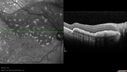

Ocular Lymphoma - non-Hodgkins - B-Cell - OCT shows multifocal sub-RPE masses 437 viewsMultifocal sub-RPE lesions in the left eye of a patient with history of Non-hodgkins B-cell Lymphoma last active 2 years agoMar 09, 2017

Ocular Lymphoma - non-Hodgkins - B-Cell - OCT shows multifocal sub-RPE masses 508 viewsMultifocal sub-RPE lesions in the left eye of a patient with history of Non-hodgkins B-cell Lymphoma last active 2 years agoMar 09, 2017